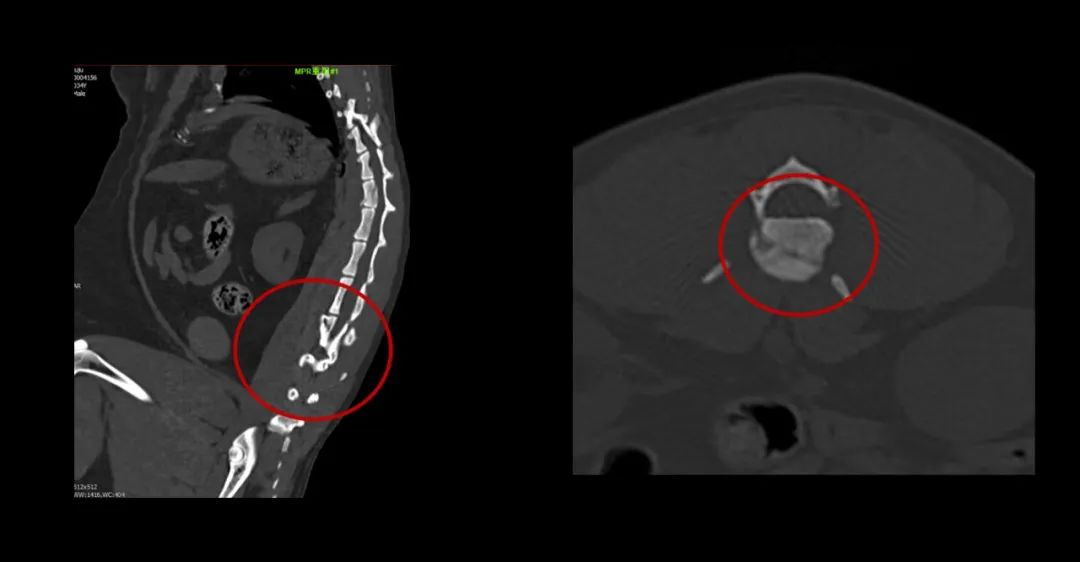

▲寵物也喜歡吃燒烤,可惜竹簽卡在食道里了。